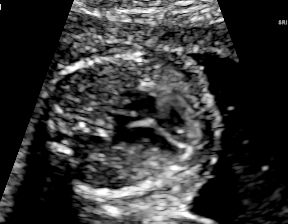

| Abdominal | Brain | Femur | Lips | |

| Device A | ![]() |

![]() |

| Device B | ![]() |

| Histogram | ![]() |

We demonstrate the practical applicability of our method on a challenging medical application, the classification of standardized fetal ultrasound (US) views during prenatal screening. In many countries, US imaging is clinical routine for prenatal health care. The classification of standardized views is important for a consistent, cross-institutional identification of possible abnormalities [47]. Early detection of pathological development can inform following treatment and delivery options [55, 25]. DNNs have shown promising performance to support this task [2]. However, ultrasound images are often hard to interpreted [40]. Anatomical structures have inconsistent appearance [2] and contain different orientations and shapes of anatomical landmarks [1]. Labeled training data is often insufficient as annotating medical images requires significant expertise and is prohibitively expensive in both time and labor. Manifestation of acoustic shadows [17, 44] as shown in Fig. 2(a) as well as different imaging devices as shown in Fig. 2(b) can lead to a domain shift problem for vanilla DNN classifiers. Exploring domain adaptation in fetal US enables DNN classifiers to be effectively utilized on a wider range, which supports identification of abnormalities from varying data sources. This can benefit prenatal healthcare.

We evaluate the proposed method on two fetal US standard plane classification tasks, where the domain shifts are respectively caused by shadow artifacts (Fig. 2(a)) and different image acquisition devices (Fig. 2(b)). For both tasks, images from source and target domains are unpaired and collected independently. We show the key results in the main paper and detailed implementation, network architectures as well as more results in the supplemental Appendix.

IV-D Experiments on cross-device fetal US

The previous experiment on fetal US images is supported by data restricted to one US imaging device. Here, we evaluate MIDNet for a standard plane classification task on data from different imaging devices (different device domains). Device A is “GE Voluson E8” which is the same device in Sec. IV-C, which acquired 2D fetal US images. Device B is “Philips EPIQ V7 G” which acquired another images sampled from about 500 2D US examinations with gestational ages between 20-32 weeks (see Fig. 2 (b)). In this experiment, we use four different anatomical standard plane locations with sufficient images in both domains, including Abdominal, Brain, Femur and Lips, which are selected by an 10-year-experienced sonographer. In this experiment, the source domain is set as device A while the target domain is device B. Training data consists of all four standard planes from the source domain as well as Abdominal and Brain from the target domain. We aim to separate anatomical features (categorical features) and imaging device features (domain features) to obtain generalized anatomical features for achieving high performance of standard plane classification on (Femur and Lips). Here, contains Abdominal, Brain, Femur and Lips from the source domain and contains Abdominal and Brain from the target domain. Hyper-parameters to in Eq. 11 are for the proposed MIDNet model and is additionally for MIDNet+.